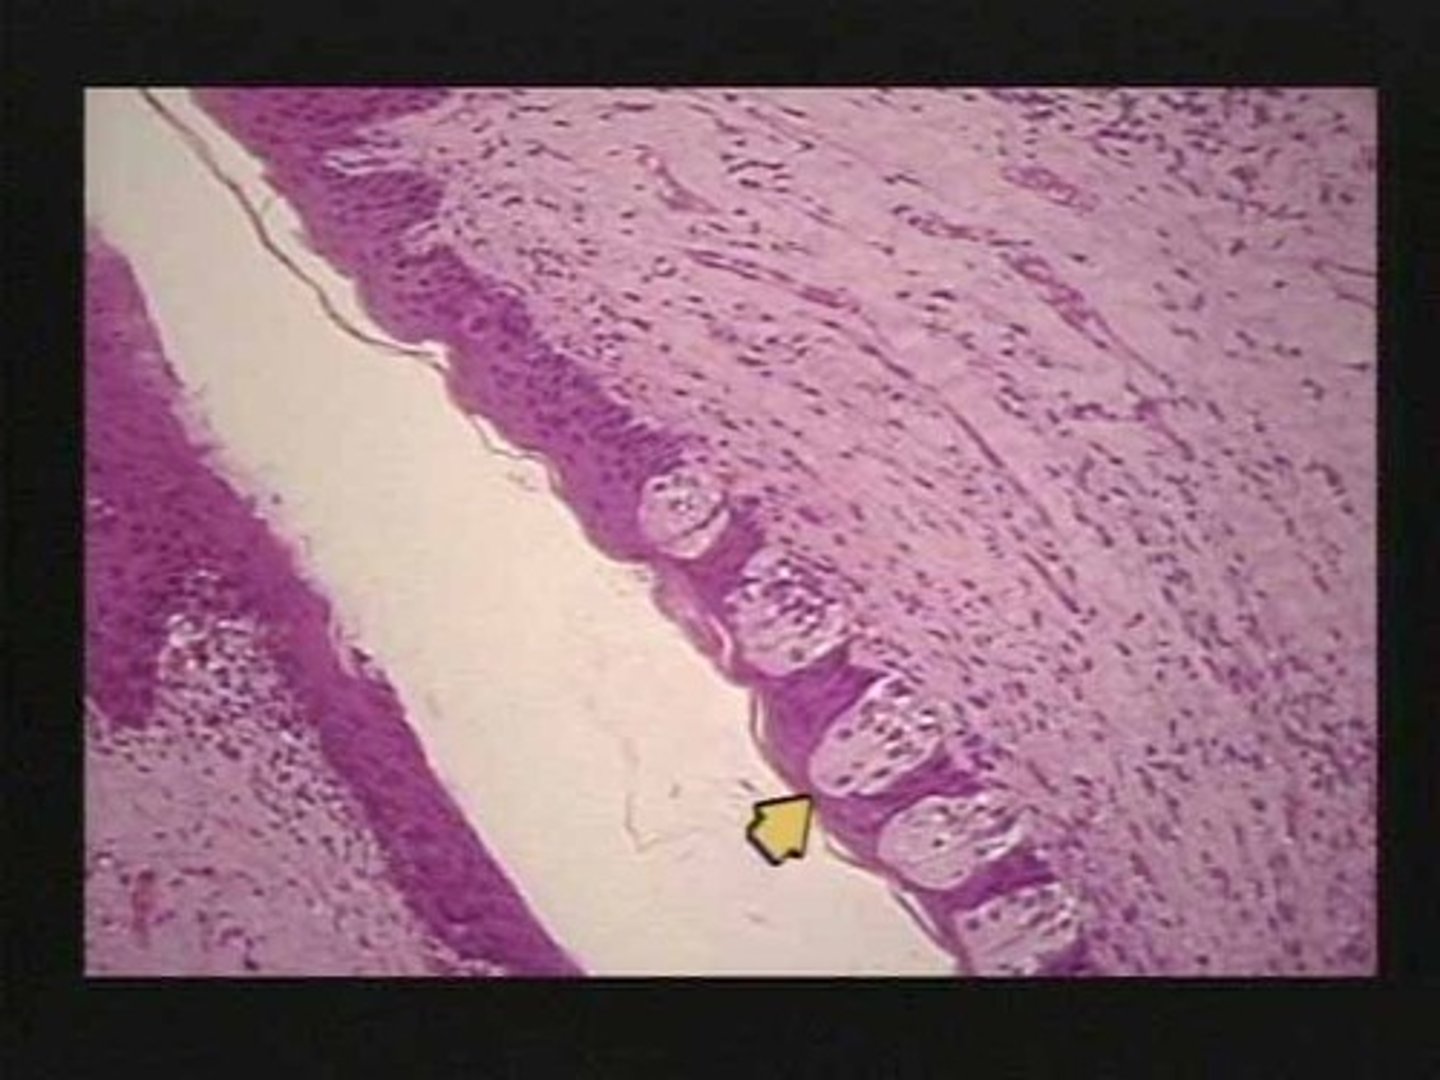

Liver lobule

Hepatocytes

Central vein

Sinusoids

Lobule

What is the functional unit of the liver?

Liver Hepatic Portal Triad

Bile ductule

Hepatic arteriole

C

Bile

What flows through the bile ductule?

Oxygen rich blood

What flows through the hepatic arteriole?

Nutrient rich blood

What flows through the hepatic portal venule

Hepatic vein

Where does blood flow after it exits the sinusoids of the liver?